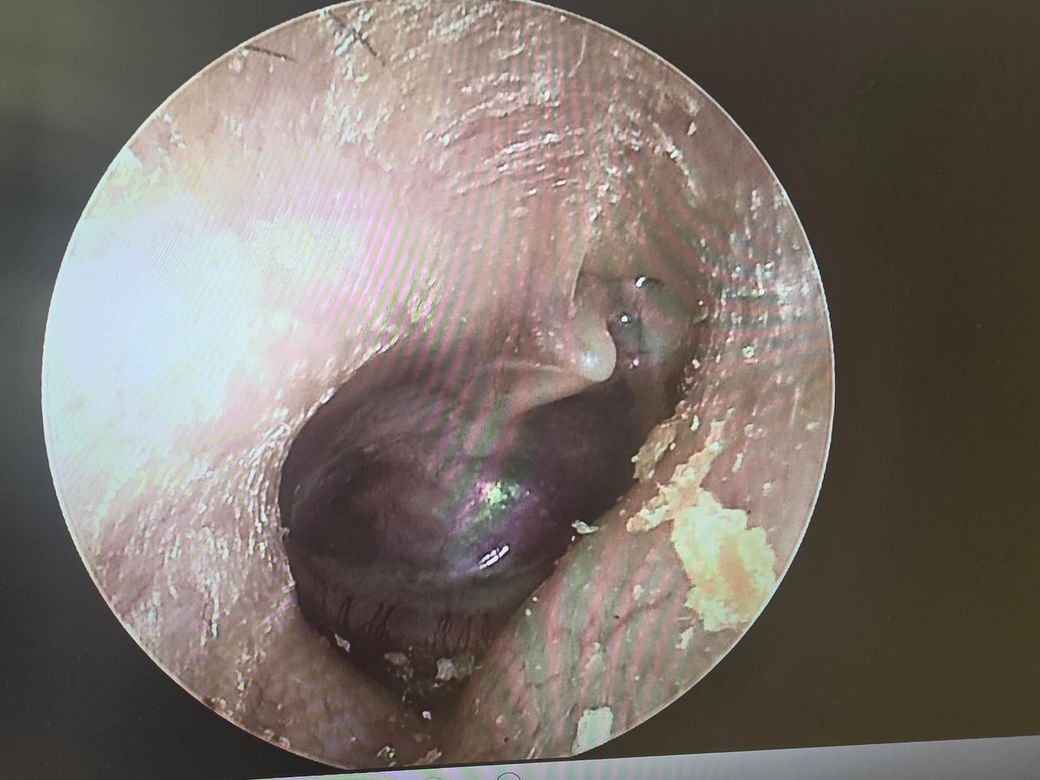

양측 고막 사진입니다. 병원마다 하는 얘기가 다릅니다. 이관은 개방이니까 플러그 넣어야한다 폐쇠니까 풍선확장술 해야한다 나뉘고요. 고막은 retraction 이랑 Adhesion 이 있다고 어느 병원에선 환기관 넣아야한다 어느병원에선 물이 차있는게 아니라서 안넣어도 된다 라고 합니다

어떤 소견이 맞고 어떤 치료방법이 맞을지 궁금하네요 그리고 현재 고막 상태는 어떤가요? 발사바 했을때 사진도 같이 첨부합니다

• 제시하신 고막 사진은 전반적으로 심한 함몰(retraction)과 일부 부위의 유착(adhesion)이 의심되는 소견입니다. 특히 고막이 중이 쪽으로 깊게 당겨져 있고, 광택이 줄어들며 특정 부위가 고정된 형태로 보입니다. 이는 단순한 일시적 음압 상태를 넘어서, 만성적인 이관 기능 이상에 의해 구조 변화가 진행된 단계로 해석하는 것이 타당합니다.

병태생리를 기준으로 정리하면, 이관 기능이 저하되면 중이 내 음압이 지속되면서 고막이 안쪽으로 빨려 들어가고, 이 상태가 지속되면 고막이 중이 구조물과 붙는 유착이 발생합니다. 이 단계에서는 단순한 이관 개방/폐쇄 개념만으로 설명이 어려워지고, “기능 이상 + 구조 변화”가 동시에 존재하는 상태로 보는 것이 맞습니다.